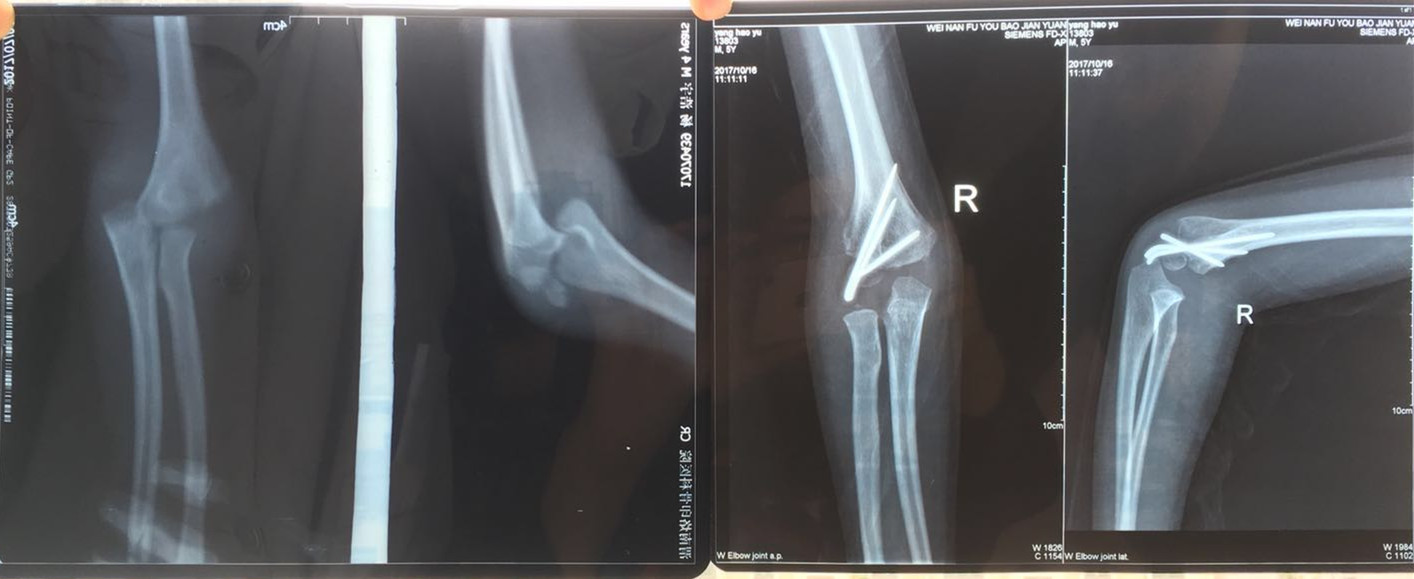

刘建军副主任医师接诊时,小西西疼痛难忍嚎啕大哭,根本不配合检查,抱着受伤的胳膊不让动,刘医生对小西西温言抚慰,趁孩子注意力转移时迅速进行手法复位石膏托固定,孩子的疼痛立即减轻,随后做了X线片和重建CT检查,诊断为:右侧肱骨外髁骨折并肘关节脱位。刘医生结合丰富的临床经验判断,单纯的手法复位治疗效果不佳,需要尽快做肘关节脱位切开复位内固定术进行治疗。

手术很快顺利完成,小西西住院一周后出院回家休养。在出院后定期复查时,刘建军副主任医师发现孩子肘关节功能恢复不佳,右侧肘关节不能屈曲伸直,就根据孩子的具体情况,耐心地指导家长帮助孩子进行功能锻炼,并多次进行电话跟踪随访治疗效果。

经过小儿外科医护人员精心的治疗和指导,加上小西西家长的积极配合,三个月后小西西再次来院复查时惊喜出现了,刘医生意外地发现伤情复杂严重的小西西肘关节功能恢复的竟然如此迅速和良好,已经可以取出内固定,随后再进行一段时间的康复锻炼,即可逐渐恢复肘关节正常的功能。